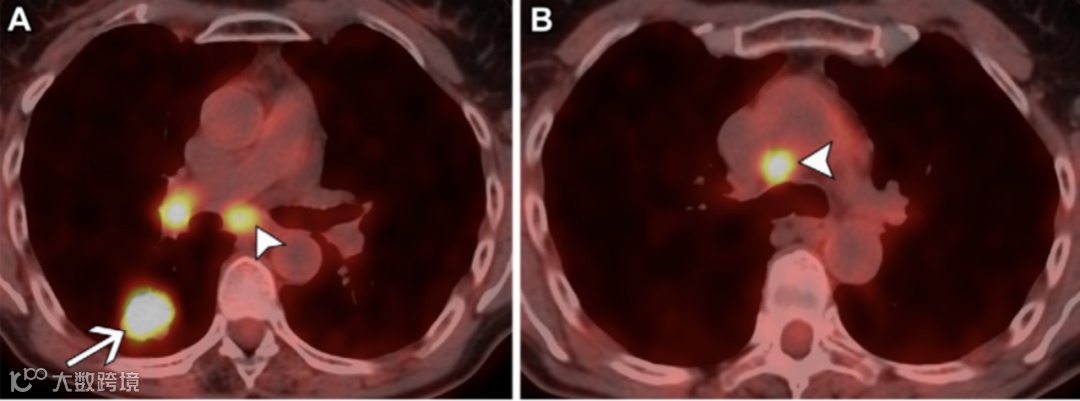

图10. 53岁女性非小细胞肺癌(NSCLC)患者的N2b期病变。

不同水平的轴位融合氟代脱氧葡萄糖(FDG)PET/CT图像显示右下叶有一个FDG高摄取肿块(A中的箭头),并且在同侧4R和7站点发现多个站点的转移性FDG高摄取N2淋巴结(短箭头)。

图11.两例N3期病变患者。

(A,B)63岁女性非小细胞肺癌(NSCLC)患者的冠状重建增强胸部CT图像(软组织窗)(A)显示左上叶原发肿瘤(箭头)直接侵犯左肺门,并且在对侧4R站点发现转移性N3淋巴结(短箭头)。与A图像相同水平的冠状融合FDG PET/CT图像(B)显示这些淋巴结(短箭头)呈FDG高摄取,类似于原发肿瘤(箭头)。

(C,D)58岁男性NSCLC患者的冠状重建未增强胸部CT图像(软组织窗)(C)显示右下叶原发肿瘤侵犯右肺门(箭头),并且在1R和1L站点发现转移性N3双侧低颈淋巴结(短箭头)。与C图像相同水平的冠状融合FDG PET/CT图像(D)显示这些淋巴结(短箭头)呈FDG高摄取,类似于原发肿瘤(箭头)。对于锁骨上淋巴结(1号站点)受累,无论是同侧还是对侧淋巴结受累,均视为N3期病变。